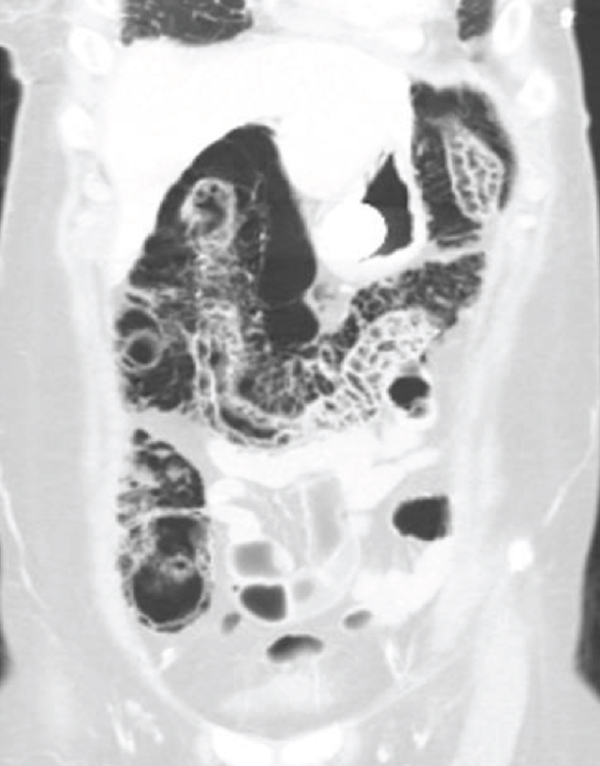

Imaging findings of pneumatosis intestinalis posttransplant are unique as compared to PI seen in other scenarios such as bowel ischemia. PI in posttransplant patients has a bubble-like/expansile appearance with a significant amount of air within the bowel wall (Figures 1 and 2). In these patients, it is helpful to view the pneumatosis on lung windows in order to properly assess its extent (Figure 3). In contrast, for PI in a patient with intestinal ischemia (Figure 4), imaging findings show more of a thin rim of gas bubbles within the submucosa without the expansile appearance. Although posttransplant PI can appear as a thin layer of gas, it would be unusual for intestinal ischemia to appear as bubble-like/expansile. Thus, if the bubble-like/expansive appearance of PI is seen, it may support a benign etiology and clinical course.

(a)

(b)

(c)